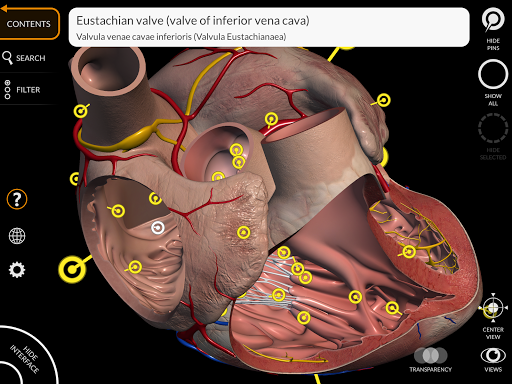

"Anatomy 3D Atlas" cho phép bạn nghiên cứu giải phẫu người theo cách dễ dàng và tương tác.

Thông qua giao diện đơn giản và trực quan, bạn có thể quan sát mọi cấu trúc giải phẫu từ mọi góc độ.

Các mô hình giải phẫu 3D đặc biệt chi tiết và có kết cấu lên đến độ phân giải 4k.

MÔ HÌNH GIẢI PHẪU 3D

• Hệ thống tim mạch

• Bằng cách chọn một mô hình hoặc một ghim, thuật ngữ giải phẫu liên quan sẽ hiển thị